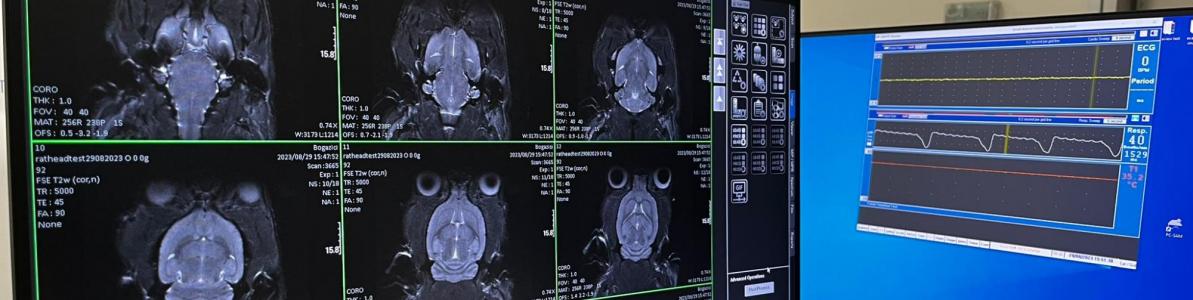

Our aim is to better understand the human brain by integrating functional neuroimaging techniques such as EEG and fMRI. We are highly interested in the interplay between systemic physiology—such as heart rate, respiration, and pupil behavior—and various states of vigilance. We are designing and developing ideas to better understand the brain and physiology.

We are conducting imaging studies including both human and preclinical models and advancing computational signal analysis techniques, enabling us to better understand the brain's structure and function in both health and disease.